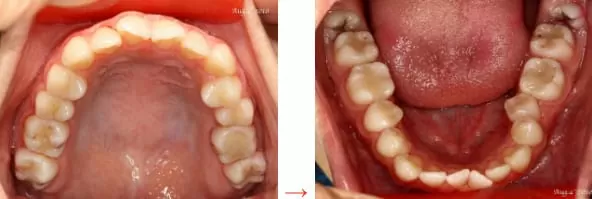

透過開刀拔牙再使用矯正方式將牙齒排列整齊,恢復牙齒及臉形的美觀。

圖2.再利用矯正方式將牙齒重新排列整齊,並符合患者牙齒的咬合型態。